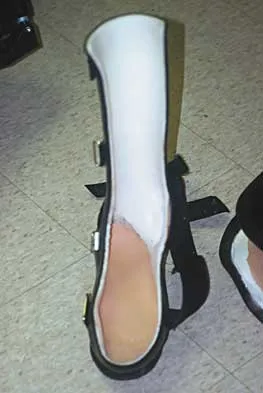

A 15-year-old boy with a type I hereditary sensory motor neuropathy (Charcot-Marie-Tooth disease) reports recurrent ankle sprains and significant pain in the hindfoot and midfoot despite orthotic management. Examination reveals that he walks with a drop foot and has dynamic clawing of the toes. Clinical photographs of the left foot are shown in Figure 7. Management should consist of